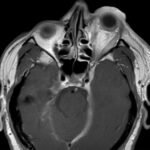

Orbital compartment syndrome (OCS) is an ophthalmologic emergency due to an acute rise in intra-orbital pressure and can result in permanent vision loss, oftentimes requiring emergent surgical decompression. Orbital compartment syndrome most commonly occurs due to recent trauma and is often easily diagnosed by history and physical exam. However, there are other causes of OCS where a more subacute/chronic rise in pressure can lead to an atypical presentation. This is a case report of a 48-year-old male who presented with left eye pain and swelling for the past 6 months. The patient had seen two ophthalmologists prior to his emergency department (ED) presentation who had prescribed him an antibiotic ointment, oral steroids, and steroid eye drops. The physical exam in the ED was concerning for increased intra-ocular pressure (IOP) and decreased vision. Ophthalmology was consulted and requested magnetic resonance angiography (MRA) to assess a vascular etiology given tortuous retinal vasculature. Emergent surgical decompression was deferred due to chronicity of symptoms, and patient was started on dorzolamide/timolol and brimonidine eye drops as well as intravenous (IV) acetazolamide with subsequent improvement in IOP. Imaging revealed a left carotid-cavernous sinus fistula (CCF), and the patient was admitted to neurosurgery. Patient successfully had an embolization with subsequent normalization of IOP and improvement of symptoms. This case is a good example of how non-traumatic causes of OCS can lead to misdiagnosis and how surgical decompression could potentially be deferred in subacute OCS.